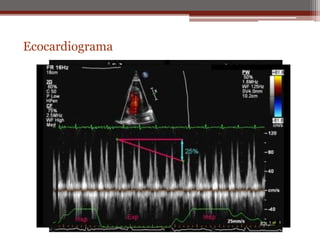

Ecocardiograma

1. Estudio más eficaz para

derrame pericárdico

2. Permite identificar

cardiomegalia por

dilatación de cavidades

o derrame pericárdico.

3. Cantidad de derrame